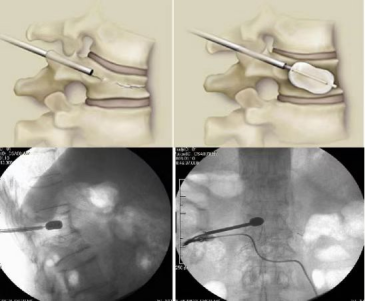

3.椎体压缩性骨折:经皮椎体成形术(球囊骨水泥)、经皮钉棒内固定治疗压缩性骨折。